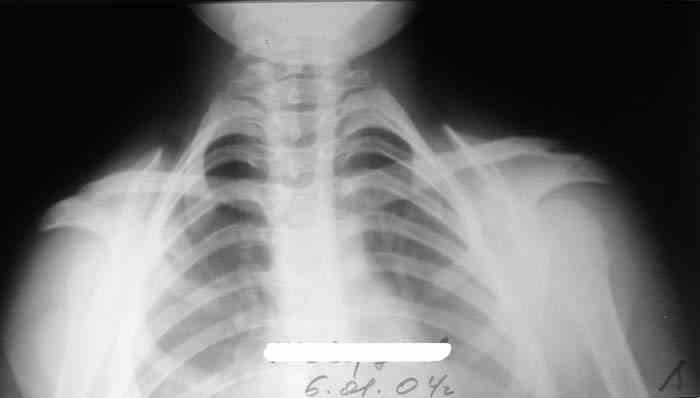

Девочка, 9 лет. Жалобы на деформацию верхнего плечевого пояса.

Объективно: приведение обоих надплечий, объем движений в плечевых суставах в полном объеме, общесоматический статус без патологии, УЗИлопаточных областей - без патологии.

Возможно речь идёт о добавочных шейных рёбрах, для уточнения целесообразно сделать боковую рентгенографию.

Больная на Вашей фотографии довольно похожа на Cleidocranial Disostosis. Пришлите снимки плечевого пояса. Это может быть недоразвитие или отсутствие ключиц.

Наличие ключиц на прямом снимке, снимает диагноз врожденного отсутствия ключиц.

Мне кажется, случай похож на Poland's Syndrom, синдром встречается при врожденной паталогии, когда отсутствует грудные мышцы (pectoralis), в большинстве случаев односторенне, и пластические хирурги рекомендует операцию.

Предлагаю пока рабочим диагнозом считать: "Врожденная аномалия грудной клетки. Добавочные шейные ребра".